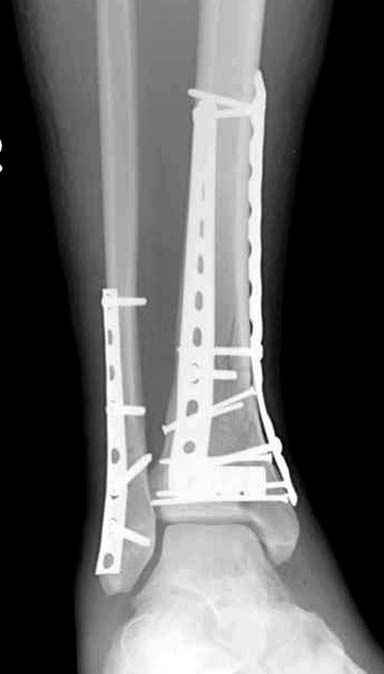

Данная фиксация пластинами сделана классическим АО методом описанным еще в 1989 году в книге J. Mast и R. Ganz “Planning and Reduction Technique in Fracture Surgery”. В то время antiglade method DCP пластиной в 4.5 мм c повторением натурального изгиба голени в н/3 считался одним из оригинальных. Повторение оригинальной концепции и фиксация спонгиозными шурупами в дистальном отделе доказывает, что коллеги хорошо освоили метод АО. Но для уменьшения раздражения пластиной изнутри в нижнем отделе, авторы применяли технику погружения пластины в кортекс. Профилактические меры не всегда помогали, и в неумелых руках "передне-медиальный АО доступ" часто осложнялся кожными осложнениями.

Приход анатомических преконтурированных тонких пластин с угловой стабильностью изменил методику лечения низких переломов. Современные пластины устанавливаются из минидоступов и разделяются на правые и левые. Можно установить латерально, медиально или спереди в полиаксиальных направлениях.

Без современных материалов создать хорошую фиксацию становится трудной задачей, и этот случай характерен тем, что достигнутую идеальную репозицию испортили старомодной техникой. Исследования показали, что спонгиозные шурупы в метафизарных частях не создают механические преимущества как считали раньше. Кортикальные винты менее агрессивны и не оставляют дефекта кости после их удаления.

Низкопрофильные преконтурированные пластины с угловой стабильностью создают меньше проблем с медиальным покрытием, а толстая пластина становится раздражителем после спадения отека.

Здесь представлены несколько примеров снимков с осложнением, медиальная пластина, медиальная в комбинации с латеральной, метод Илизарова, а также сравнительные данные толщины медиальных пластин Synthes 4.4 mm, DePuy 3.2 mm.